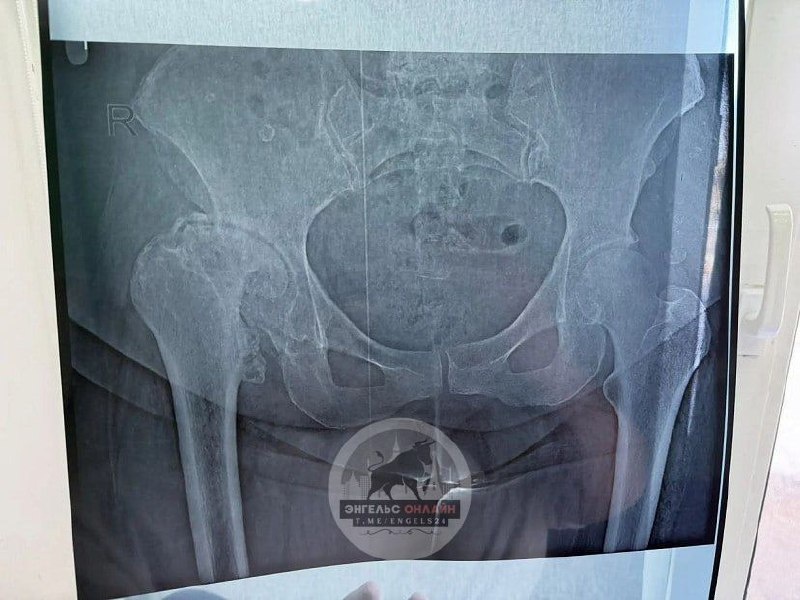

Как рассказали в медучреждении, женщина 1967 года рождения поступила к ним из Волгограда. У пациентки был диагностирован диспластический правосторонний коксартроз 3-й степени, осложненный врожденным вывихом головки тазобедренного сустава. В детстве женщине неоднократно проводили закрытое вправление сустава.

Энгельсские медики провели тотальное эндопротезирование сустава, сделали пластику верхнего края вертлужной впадины.

«Это вмешательство предполагает замену пораженного сустава искусственным протезом, позволяющим восстановить подвижность и облегчить боль пациента», - пояснили специалисты.